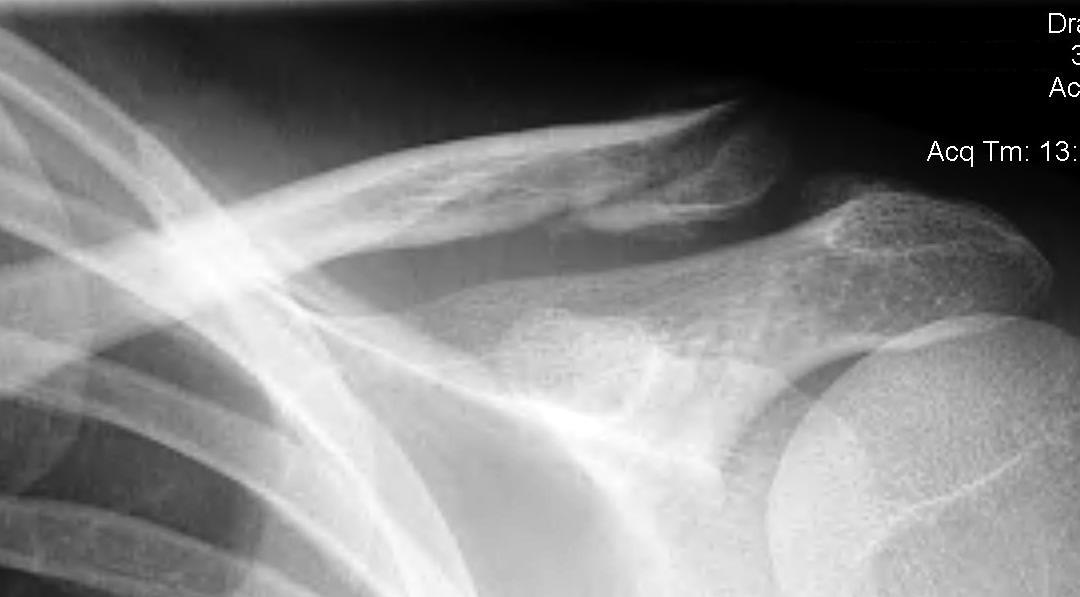

Neer Classification

Fracture lateral to the CC ligaments Non displaced

|

Fracture medial to the CC ligaments CCL ligaments attached to lateral fragment Medial fragment displaced superiorly |

Between conoid and trapezoid Conoid disrupted Trapezoid remains attached to the lateral fragment |

Lateral to CC ligaments Intra-articular extension Stable |

Periosteal sleeve disruption Pediatric Medial fragment displaced |

Comminuted Type II Medial fragment displaced |

Type I

Type II

Type V